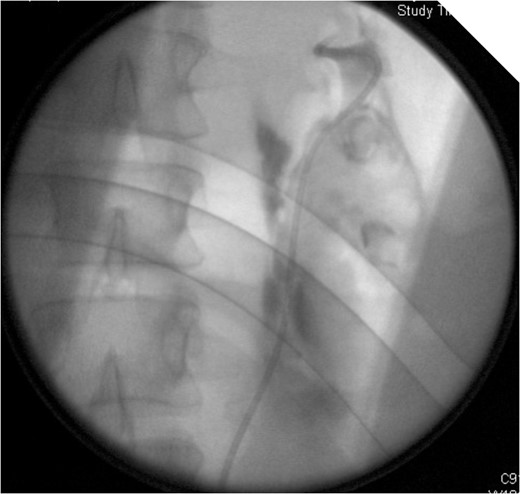

On table Pyelogram confirmed intact left collecting system and ureter.

On stent removal, we performed an on table retrograde pyelogram to confirm there is no residual leakage and also to exclude significant stricturing. A CT IVU after stent removal may also be considered as an alternative to this approach.